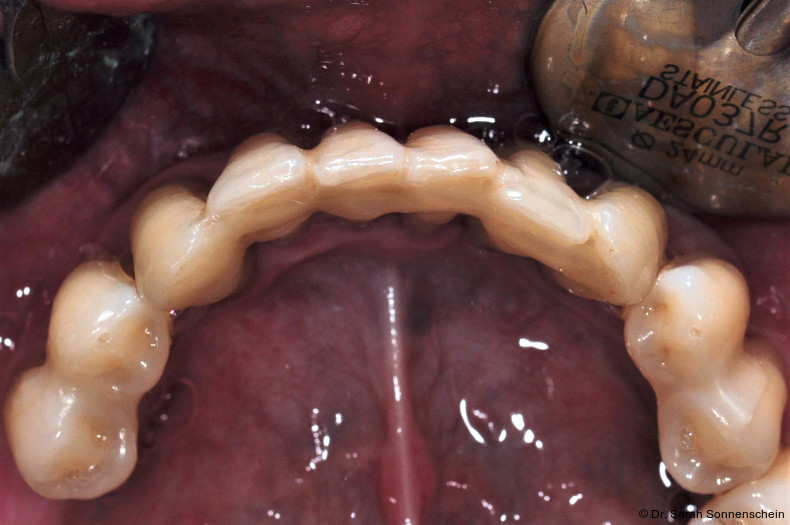

Die Abbildungen 2a–d zeigen die Eingangssituation einer allgemeinmedizinisch gesunden 37-jährigen Nichtraucherin mit Parodontitis Stadium IV Grad C, Falltyp 1 (damalige Diagnose: generalisierte aggressive Parodontitis). Ihr Hauptanliegen war der Zahnerhalt und die Beseitigung der „lockeren“ Zähne. Die Sondierungstiefen lagen generalisiert zwischen 5 und 9 mm. Die AV bei bis zu 12 mm. Die Zähne 33-43 wiesen alle einen Lockerungsgrad III auf. Auch die Oberkieferfront wies einen Lockerungsgrad II auf. Nach der Mundhygienephase erfolgte eine Full-Mouth-Disinfection mit adjuvanter Antibiotikagabe. Die Schienung der Zähne 33-43 erfolgte mittels glasfaserverstärkter Kompositverblockung. Bei Befundevaluation zeigten sich nur noch vereinzelte Taschen von bis zu 5 mm, welche reinstrumentiert wurden. Die Patientin konnte entsprechend in die engmaschige UPT (dreimonatiges Intervall) überführt werden. Zur Verbesserung der Ästhetik und Stabilisierung der gelockerten Oberkieferfrontzähne erfolgte nach Abschluss der aktiven Behandlungsphase ebenfalls eine Verblockung der Oberkieferfrontzähne und Zahnumformung im direkten Verfahren mittels Komposit. Abbildungen 3a–d zeigen die Situation der Patientin zweieinhalb Jahre nach Erstbefundung.